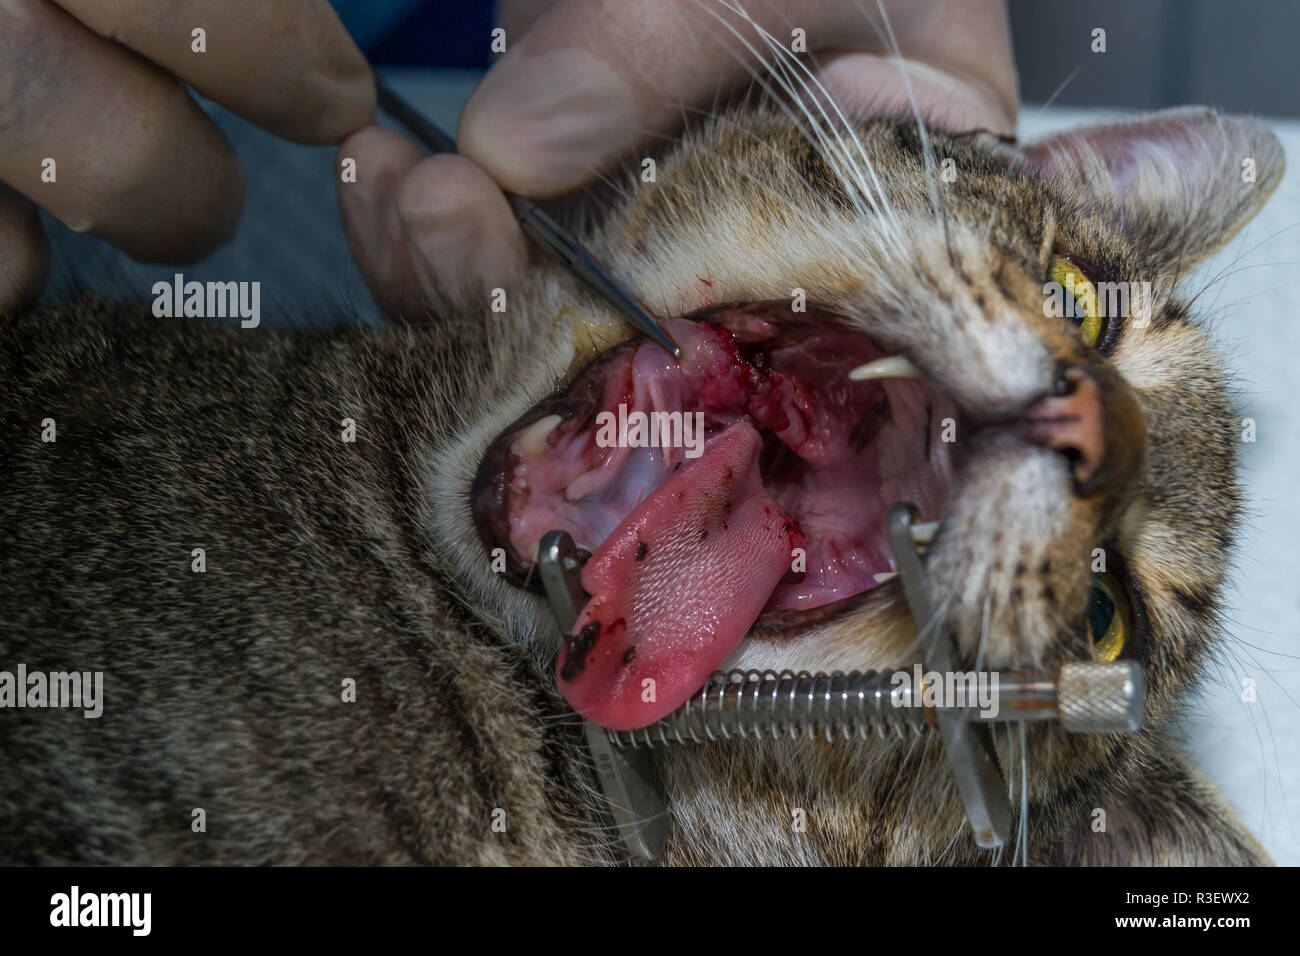

Katze mit tonsillitis, Mandeln entfernen mit elektrokauter, orale Chirurgie in Haustiere Stockfotohttps://www.alamy.de/image-license-details/?v=1https://www.alamy.de/katze-mit-tonsillitis-mandeln-entfernen-mit-elektrokauter-orale-chirurgie-in-haustiere-image225906674.html

Katze mit tonsillitis, Mandeln entfernen mit elektrokauter, orale Chirurgie in Haustiere Stockfotohttps://www.alamy.de/image-license-details/?v=1https://www.alamy.de/katze-mit-tonsillitis-mandeln-entfernen-mit-elektrokauter-orale-chirurgie-in-haustiere-image225906674.htmlRFR3EX7E–Katze mit tonsillitis, Mandeln entfernen mit elektrokauter, orale Chirurgie in Haustiere

Katze mit tonsillitis, Mandeln entfernen mit elektrokauter, orale Chirurgie in Haustiere Stockfotohttps://www.alamy.de/image-license-details/?v=1https://www.alamy.de/katze-mit-tonsillitis-mandeln-entfernen-mit-elektrokauter-orale-chirurgie-in-haustiere-image225906410.html

Katze mit tonsillitis, Mandeln entfernen mit elektrokauter, orale Chirurgie in Haustiere Stockfotohttps://www.alamy.de/image-license-details/?v=1https://www.alamy.de/katze-mit-tonsillitis-mandeln-entfernen-mit-elektrokauter-orale-chirurgie-in-haustiere-image225906410.htmlRFR3EWX2–Katze mit tonsillitis, Mandeln entfernen mit elektrokauter, orale Chirurgie in Haustiere

Katze mit tonsillitis, Mandeln entfernen mit elektrokauter, orale Chirurgie in Haustiere Stockfotohttps://www.alamy.de/image-license-details/?v=1https://www.alamy.de/katze-mit-tonsillitis-mandeln-entfernen-mit-elektrokauter-orale-chirurgie-in-haustiere-image225906377.html

Katze mit tonsillitis, Mandeln entfernen mit elektrokauter, orale Chirurgie in Haustiere Stockfotohttps://www.alamy.de/image-license-details/?v=1https://www.alamy.de/katze-mit-tonsillitis-mandeln-entfernen-mit-elektrokauter-orale-chirurgie-in-haustiere-image225906377.htmlRFR3EWTW–Katze mit tonsillitis, Mandeln entfernen mit elektrokauter, orale Chirurgie in Haustiere